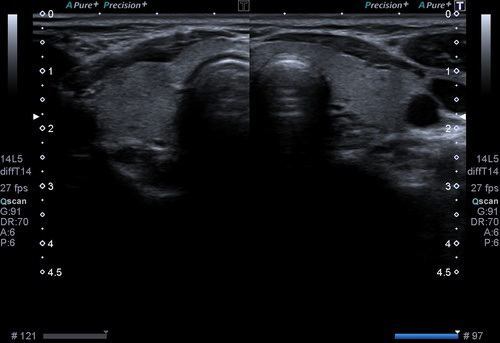

TİROİD ULTRASONU

Tiroid nodulleri tiroid bezi içerisindeki yuvarlak şekilli kitlelerdir. Tek ya da çok sayıda olabilirler. Bu noduller aşırı hormon salgılayarak hipertroidiye ya da hormon salınımını azaltarak hipotroidiye yol açabilirler. Her iki durumda da medikal tedavi gerekir. Nodullerin ultrasonogrfai incelemesindeki radyolojik özelliklerine göre, takip aralığı ya da biyopsi yapılıp yapılmayacağına karar verilir. Takip ultrasonlarda daha önce tarif edilen nodullerde yapısal bir takım değişiklikler olması, boyutlarında anlamlı büyüme olması durumunda da biyopsi yapılması gerekir. Ultrason ile noduller dışında tiroid bezi büyüklüğü de ölçülür ve takip edilir. Büyüme olması durumunda çevre dokular ile ilşikisi, göğüs kafesi içerisine uzanıp uzanmamsı değerlendirilerek olası cerrahi için cerraha yol gösterici bilgiler verilir.